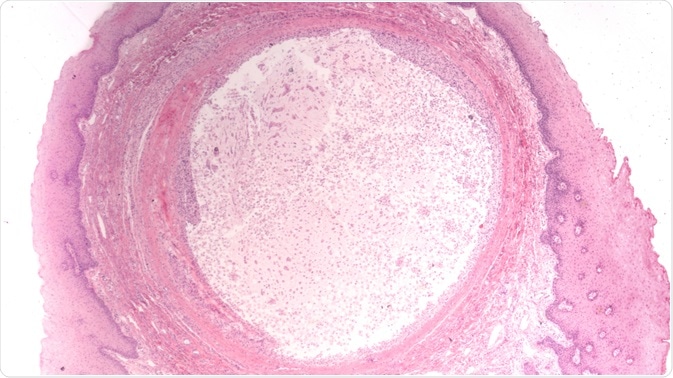

mucoceleMicroscopic image of a mucocele (mucus cyst). Image Credit: David A Litman / Shutterstock.com